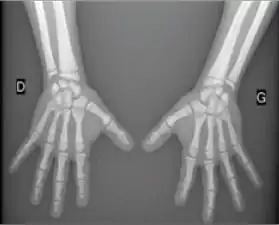

Acroosteolysis

Acroosteolysis is resorption of the distal bony phalanges. Acroosteolysis has two patterns of resorption in adults: diffuse and bandlike.

The bandlike pattern of resorption may be seen with polyvinyl chloride exposure and Hadju-Cheney syndrome.[1]